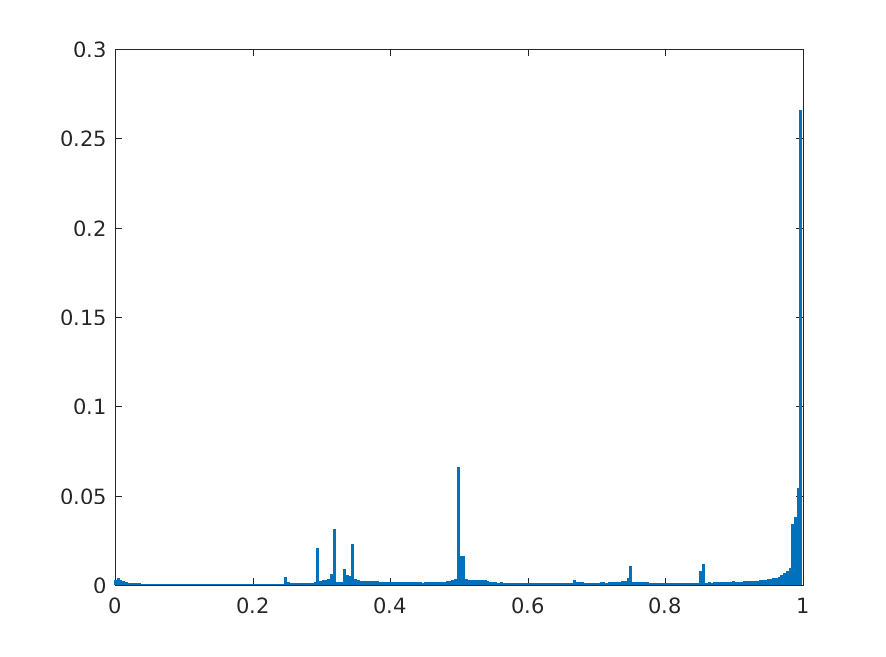

8 Additional Examples of Localization

In this section we show more examples of localization. Few localization samples are shown in Fig. 11. It can be observed that, in the CXRs with Cardiomegaly (Fig. 11(a) and (b)) a fine localization around the heart is observed. In the normal CXRs (Fig. 11(c) and (d)) such localization is not observed. Rather the lowest probabilities are spread out in the CXR image. It is interesting to note that, the localization algorithm gets low probability where the heart is enlarged during cardiomegaly, but the proportion is small compared to the localization in other areas of normal CXRs. In order to observe the performance of the heat map we computed histograms of heat maps of each of the 100 CXRs in the test set for Cardiomegaly detection and average histograms are shown in Fig. 11(e) and (f) for CXRs with Cardiomegaly and normal CXRs, respectively. It is to be noted that, the histograms include both success and failure cases. It can be observed that, for CXRs with Cardiomegaly the classifier is highly sensitive toward Cardiomegaly detection even under occlusion. This indicates that, the classifier primarily looks for local features in a CXR instead of some feature that is spread out in the entire CXR. However, the classifier is not sensitive toward normal CXRs under occlusion. Rather, the probabilities are spread out in the probability spectrum. After that, we analyzed the failure cases where the classifier is unable to classify the image correctly. Two such examples of failure cases are shown in Fig. 12. The localized CXR shown in Fig. 12(a) contains Cardiomegaly whereas the classifier detects it as normal. However, the localization shows that it localizes around heart quite well despite the in accurate classification. On the other hand, Fig. 12(b) shows an example of normal image which has been classified as Cardiomegaly by the classifier. There is stronger localization around the hear that that is observed for normal images as in Fig. 11(c) and (d), however, like those images the localization is spread out.

In a similar fashion, additional localization results for Pulmonary Edema is shown in Fig. 13. In Fig. 13(a) and (b) localization of two examples of CXRs with Pulmonary Edema is shown. As stated earlier the classifier localizes in the lung region. This is not the case when normal images are used to localize Pulmonary Edema as seen in Fig. 13(c) and (d). The localizations are obtained in random dense locations such as the sternum or heart. Like the cardiomegaly case, the histogram averages for CXRs with pulmonary Edema (Fig. 13(e)) shows a sensitivity toward pulmonary edema detection while the normal CXRs shows a spread out detection. It is interesting to note that, in the histogram of normal images high probability (¿0.85) is non-existent, thus ensuring low false positive rate. In the test set none of the normal images have been diagnosed as Pulmonary Edema. The failure cases are shown in Fig. 12. These CXRs are with Pulmonary Edema. However, the localization algorithm shows that one of them localizes in lungs whereas the other one shows a localization pattern similar to that obtained in normal CXRs.